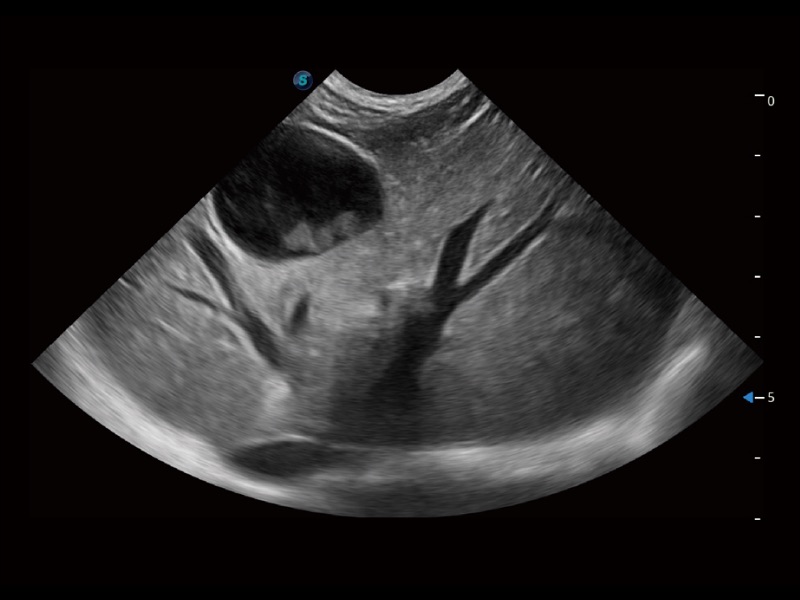

大型犬、马科、农场动物及大型异宠动物

通过创新的 Matrix E自适应滤波器和超长时间域算法,极大提升超低速微细血流的检出能力,同时更精准地滤除软组织和噪声信号,为兽用医生提供以往无法通过常规血流获得的疾病诊断信息。

ProPet 70专为动物医生设计,对不同的动物体型和生理结构作出了针对性的优化。通过动物影像专用软件,可满足个性化的应用需求,帮助动物医生获得更精确的诊断数据。